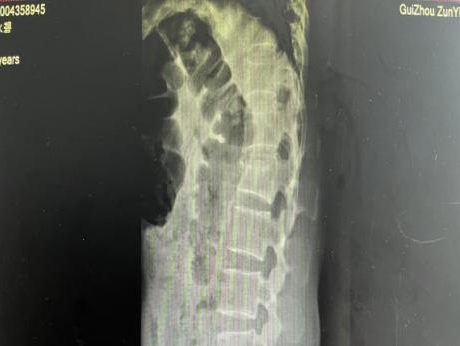

2025年11月1日,由遵义市医学会手外科分会主办、遵义市第二城市医疗集团(贵州航天医院)承办的遵义市医学会手外科分会学术交流会暨贵州省继续医学教育项目《急诊手外伤治疗临床研究新进展专题研讨班》在贵州航天医院成功举办,汇聚了遵义市手外科领域专家及基层医疗骨干,通过专题研讨与临床经验分享,共探急诊手外伤诊疗新进展。 会议特邀遵义市医学会手外科分会主任委员金文虎教授,遵义市医学会手外科分会副主任委员张子阳教授,遵义市医学会手外科分会常务委员杨绍浦教授,贵州航天医院陈明勇教授、赵兴东教授等遵义市手外伤专家进行交流分享;贵州航天医院党委委员、副院长彭亮参加会议并致辞,贵州航天医院骨科医务人员,遵义市第二城市医疗集团成员单位及红花岗区、绥阳县、桐梓县等区县医疗机构手外伤骨干参与。 贵州航天医院党委委员、副院长彭亮致辞 学术交流 本次学术交流以“急诊手外伤治疗临床研究新进展”为主题,通过理论授课与临床案例结合,共同探讨急诊手外伤临床诊疗全链条诊疗策略、关键技术、临床研究新进展,促进规范化诊疗技术向基层下沉,助力提升区域手外伤应急处置与修复能力。 贵州航天医院赵兴东教授分享《急诊手外伤的诊断与治疗原则》 贵州航天医院陈明勇教授分享《开放性骨折的治疗原则》 贵州航天医院张军教授分享《甲沟炎Winograd手术的临床应用》 贵州航天医院赵兴东教授分享《手部常见的皮肤缺损及治疗原则》 贵州航天医院张艳金教授分享《开放性骨折的清创术》 贵州航天医院冷家雄教授分享《下肢创面修复的常用皮瓣之股前外侧皮瓣》 贵州航天医院邬夏荣教授分享《踝关节慢性不稳的诊治》 贵州航天医院卢懿明教授分享《掌骨骨折》 贵州航天医院张艳金教授分享《手部肌腱的解剖与修复方法》 本次研讨班为遵义市手外科领域医务人员提供了深度交流契机,强化了医疗机构间的协作网络,进一步推动学科创新与临床实践融合,为健康遵义建设注入新动能。 贵州航天医院骨科专家简介 陈明勇 骨一科主任,副主任医师 临床擅长:从事创伤骨科工作约20年,对骨缺损、骨不连、骨肿瘤、肢体畸形等的肢体矫形重建及功能重建,慢性化脓性骨髓炎的根治治疗、糖尿病足的保肢治疗、快速康复理念(ERAS)下的老年骨折的诊治,四肢复杂骨折的诊治,四肢骨折等微创手术治疗具有丰富的临床经验。 2004年毕业于遵义医学院临床专业,曾在中国人民解放军总医院、广西医科大学第一附属医院、上海第六人民医院骨科进修。中国中西医结合学会骨伤科专业委员会横向骨搬移治疗糖尿病足及微血管网再生学组首届委员,遵义市医学会创伤分会常务委员。 瞿 晖 骨科党支部书记,骨二科主任,副主任医师 临床擅长:对骨科的常见病、关节外科、脊柱外科及运动医学疾病的诊治具有丰富的临床经验,熟练掌握骨科手术操作技术。 毕业于遵义医学院临床医学系,2005年前往广州中山大学第一附院骨显微医学部进修学习,2011年前往成都华西医院进修学习,并多次在省内外学习骨科相关知识,是中华医学会骨科分会会员。 赵小锋 中共党员,骨二科副主任,副主任医师 临床擅长:从事骨科临床工作11年,对骨科常见病、多发病诊疗有较为丰富的临床经验,擅长脊柱相关疾病诊断及治疗,尤其是颈、腰、腿疼痛疾病诊断及治疗,擅长胸腰椎骨折微创经皮穿刺内固定术、经皮穿刺椎体成形术、经皮穿刺脊柱内镜下腰椎间盘摘除术、单纯开创腰椎间盘摘除术、腰椎滑脱复位椎间植骨椎融合内固定术、腰椎管狭窄减压融合内固定术及人工髋、膝关节置换术等。 2012年毕业于遵义医学院外科学专业硕士研究生,2019年参加“遵义市115医学人才精英计划”于上海交通大学第一附属医院培训学习,2023年于北京大学第三人民医院脊柱外科进修学习,曾获得遵义市优秀医师荣誉称号。 遵义市手外科第一届委员,遵义市医学会创伤分会第一届委员,遵义市医学会创伤分会第二届委员,贵州省康复医学会第三届脊柱脊髓专业会委员,遵义市医学会烧伤与整形外科学分会委员,发表论文5篇,其中国家级核心期刊1篇,SCI论文1篇,主持市级课题1项并结题,参与市级课题2项。 赵兴东 骨科主任医师 临床擅长:擅长骨科的常见病及各种创伤、四肢骨折创伤修复、骨感染、手足疾病的诊治和手足体表畸形的矫形整复,熟练掌握骨科四肢骨病及创伤的手术操作技术,尤其在四肢关节复杂性损伤、手足外伤、组织缺损创面、难治创面的皮瓣修复方面及平足、高弓足矫形方面及四肢慢性疼痛诊治、康复方面具有丰富的临床经验。 硕士研究生,毕业于遵义医学院临床外科系,2015年前往山东省立医院手足外科进修学习;遵义市医学分会创伤分会第一、二届委员,遵义市手外科医学会第二委届员会常务委员;在省级及省级以上期刊发表文章9篇,参编著作2部,参与主持并完成市级课题1项,参与市级课题2项、省级课题1项。 张艳金 中共党员,骨科副主任医师 临床擅长:从事骨外科工作16年,对复合伤、多发伤的救治、四肢骨干骨折、关节周围骨折、骨肿瘤、骨髓炎等诊治具有丰富的临床经验。 中共党员,硕士研究生,2006年本科毕业于山西医科大学第二临床医学院,2011年研究生毕业于北京军区总医院;在“老年COPD患者合并髋部骨折的诊治”国际合作课题组研究两年,在老年髋部骨折的诊治方面具有丰富的经验,并发表论文6篇;主持遵义市级课题1项,承担遵义医科大学的临床教学工作,获得遵义医科大学优秀带教老师荣誉。编撰有《骨科疾病诊疗精粹》一书,开展2项新技术,编撰地方规范《务川自治县创伤骨科常见疾病诊疗规范》一书。 张俊凯 骨科副主任医师 临床擅长:从事骨科临床工作28年,对创伤骨折、骨感染、骨缺损、骨不连等外科诊治,四肢骨折的微创手术治疗,四肢复杂骨折(如关节内粉碎性骨折、多发骨折等)的损伤控制及手术治疗等具有丰富的临床经验。 1995年毕业于遵义医学院临床专业,2009年前往复旦大学附属医院骨科进修1年。 卢懿明 中共党员,骨科副主任医师 临床擅长:从事骨科工作18年,对创伤骨折、四肢骨折的微创手术治疗、四肢复杂骨折(如关节内粉碎性骨折、多发骨折等)的损伤控制及手术治疗,尤其是髋部骨折的PFNA等微创技术,踝关节骨折、膝关节周围骨折的Mipo微创技术等具有丰富的临床经验,开展了4项新技术,发明6项新型专利技术。 2005年毕业于遵义医学院临床专业,2017年,前往南方医科大学第三附属医院骨科进修半年,回院后运用Mipo技术对骨干骨折及干骺端骨折的治疗技术,同时积极开展骨盆骨折、髋臼骨折腹直肌外侧切口的应用;发表了多篇专业论文,经常参与省内外学术交流会授课,获得医院荣誉称号多个。 邬夏荣 骨科副主任医师 临床擅长:从事骨科工作16年,对四肢复杂骨折、骨肿瘤的诊治,尤其是足踝创伤、慢性踝关节损伤、平足症等诊疗具有丰富的临床经验。 2006年毕业于遵义医科大学临床医学专业,曾在陆军军医大学西南医院进修学习,发表多篇骨科学术论文。 余德怀 中共党员,骨科副主任医师 临床擅长:从事骨科工作10余年,对运动医学、骨关节、脊柱外科常见病、多发病的诊治具有丰富的临床经验。 硕士研究生,2011年毕业于遵义医学院临床医学专业,曾前往遵义医科大学附属医院运动医学专业进修学习;是贵州省医学会运动医学分会青年委员,西部关节镜联盟委员;发表多篇骨科学术论文。 冯 乾 骨科副主任医师 临床擅长:从事骨科工作近20年,熟练掌握骨科多发病及常见病的诊治,尤其对脊柱退变性疾病的诊断及治疗具有丰富的临床经验,主要研究脊柱微创相关治疗方式,能熟练开展椎间孔镜及UBE。 曾前往北京大学第三医院进修学习疼痛及椎间孔镜、首都医科大学友谊医院专业进修脊柱内镜;是贵州省康复医学会第三届脊柱脊髓专业委员会委员;发明专利3项、发表脊柱外科专业论文多篇。 贵州航天医院骨科简介 基本情况 贵州航天医院(原3417医院)骨科组建于1968年,前身是以创伤和断肢(断指)再植闻名于世的上海市第六人民医院骨科,中国断肢(断指)再植的奠基者、中科院院士陈仲伟等专家莅临科室指导医疗和教学,并在70年代开展了贵州省首例断肢(断指)再植手术。组建50余年来,诊治患者已逾百万,挽救了无数的伤病员,成为了保障遵义地区人民群众健康的重要支撑。 经过几代人的不懈努力,今天的骨科,已由创伤骨科发展至骨病、骨肿瘤、骨结核等领域,现有脊柱外科、关节外科、四肢创伤、手足外科四个亚专科,成为了集医疗、教学、科研于一体的综合学科,是贵州省临床重点专科、遵义市临床重点专科、遵义市骨科临床医学中心、遵义市基层骨科专科联盟理事长单位。 科室目前开放床位110张,共有医护人员50余人,副高级以上专家18人,硕士研究生15人。拥有一流骨科医疗设备多台,每年不定期选派优秀技术骨干到全国各大知名医学院校进修、学习、参观、交流,并邀请国内、国外知名专家教授来院进行交流、指导,通过不断引进国内外先进的诊疗技术,科室医疗技术水平稳步提升,为广大人民群众提供了优质的医疗服务。 专科特色 骨一科 (一)骨缺损、骨不连的肢体与功能重建 胫骨横向骨搬移技术治疗糖尿病足: (二)慢性骨髓炎的根治治疗 (三)肢体缺血性疾病如糖尿病足、脉管炎的保肢治疗 (四)皮瓣修复 (五)复杂创伤的治疗 (六)老年髋部骨折及小儿骨折快速手术 老年髋部骨折: 骨二科 (一)胸腰椎骨折微创经皮椎弓根螺钉固定术 (二)老年性骨质疏松性患者腰椎滑脱脊柱内固定术(骨水泥螺钉) (三)V形双通道脊柱内镜技术(VBE)腰椎融合术治疗腰椎退行性疾病 (四)老年性骨质疏松性骨折(PVP/PKP)术 (五)人工髋关节置换术 (六)双侧股骨头坏死人工全髋关节置换 (七)右侧全髋置换术后假体周围骨折翻修 (八)人工膝关节置换术 (九)人工膝关节假体松动翻修 (十)关节镜技术 传统手术切口 关节镜技术切口 诊疗范围 骨一科 1.四肢创伤、矫形。 2.手、足踝外科。 骨二科 End